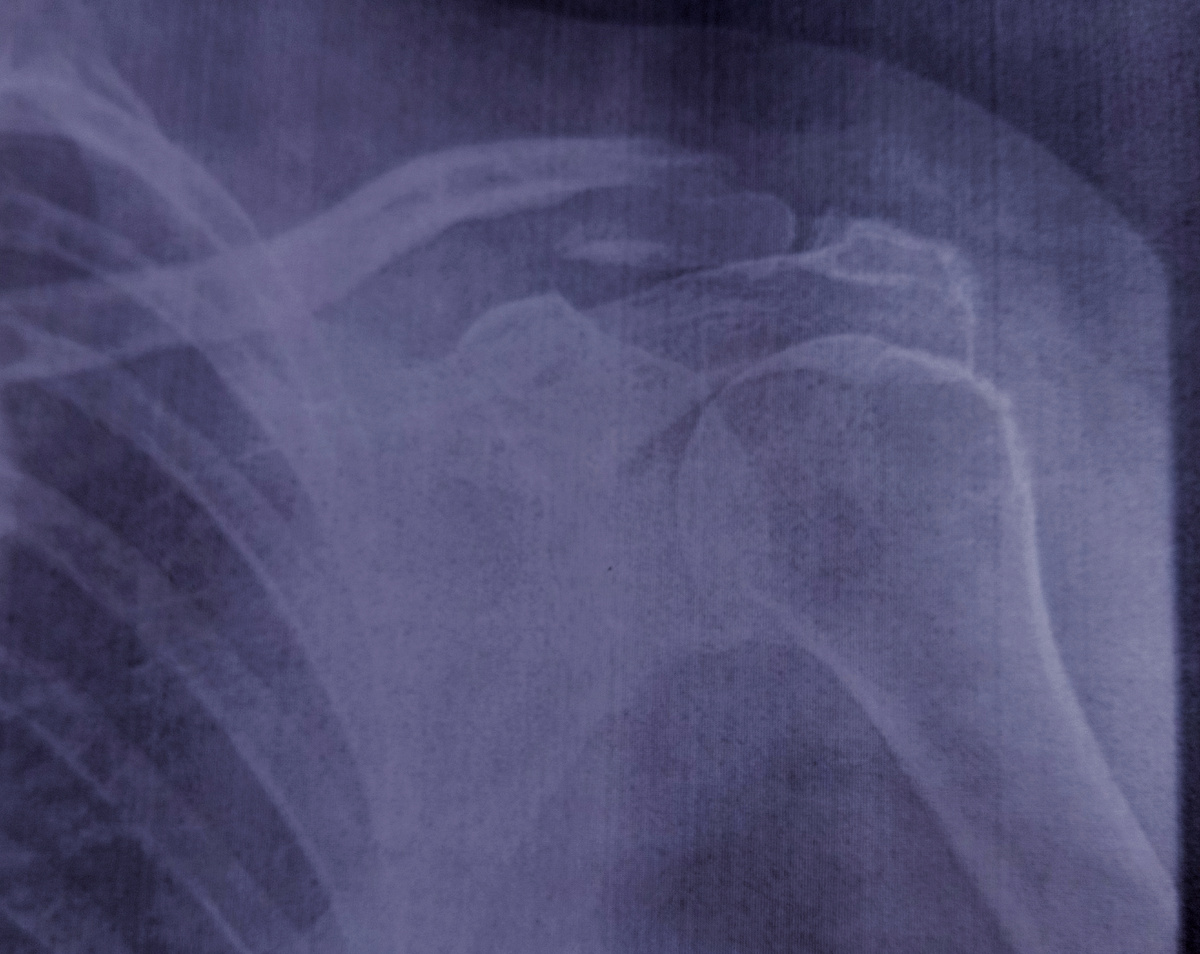

Женщина пришла , 68 лет , на снимок ключицы.

Назначена ключица и плечевой.

Я очень не люблю такие назначения, во-первых , лишняя лучевая нагрузка на пациента , а во-вторых можно и на один снимок уместить эти области интереса.

Решаю сделать только ключицу, гляну на снимок , если есть подозрения на перелом плечевого , тогда можно его снять отдельно.

Конечно, ключица сломана.

На счет сустава я пригласила травматолога, не поленилась сбегать за ним.

–Ну , что думаете , надо ей плечевой?-спросила я.

–Да нет, не надо , это от ключицы иррадиирует ей в плечо, да тут еще , походу и АКС(акромиально-ключичное сочленение), –разглядывает снимок Андрей Игоревич.

-Что будете делать с таким переломом? –заинтересованно спросила я.

–Да мы –ничего , колечки(Кольца Дельбе, прим. автора) наденем , но репонировать не полезем , в стационаре пусть делают.